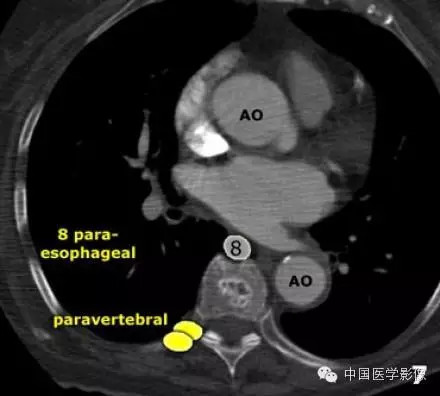

8区:食管旁淋巴结,是3P向下的延续,自隆突下沿食管延伸至膈肌食管裂孔。

8 食管旁